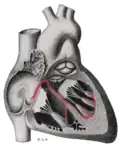

![]() Sinoatrial node shown at 1. The rest of the conduction system of the heart is shown in blue. | |

Additional images

Heart; conduction system (SA node labeled 1) -